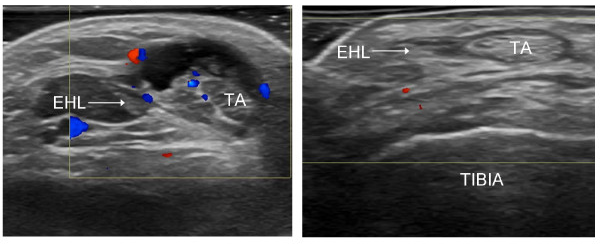

초음파 검사에서는

힘줄 주변 염증으로

까맣게 물이 고인 것이 나타납니다.

좌측: 전경골근 건초염 / 우측 : 정상

초음파에서 나타나는

활막의 상태,

삼출액의 에코도,

도플러 소견을 참고하면

급성과 만성 여부도 알 수 있습니다.

장지신근의 만성 건초염